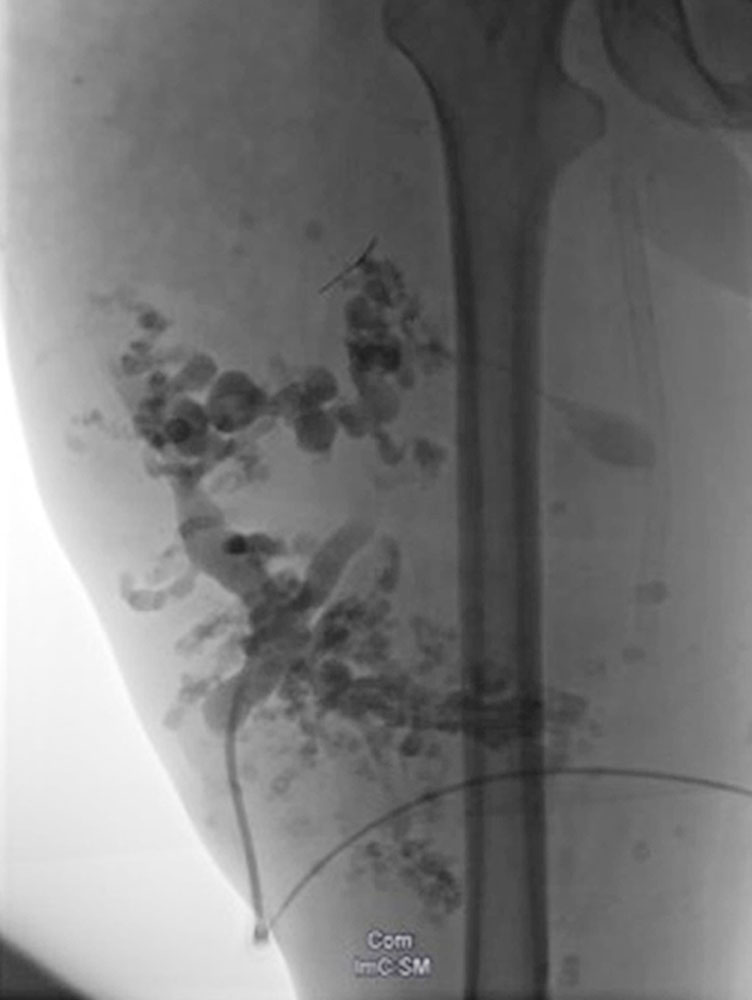

Die begleitenden Gefäßmalformationen treten nicht immer auf, sind jedoch, neben der erhöhten Wahrscheinlichkeit für das Auftreten von Tumoren, oft bestimmend für den Krankheitsverlauf beziehungsweise die Symptomatik. Relativ charakteristisch sind die als PHOST (PTEN Hamartoma Of Soft Tissue) bezeichneten, oft progredienten, umschriebenen Weichteilgewebsveränderungen, die sich histologisch als gemischte Gefäß- und Weichteilgewebsmalformationen darstellen (kapilläre, venöse und lymphatische Malformationen), die in atypisch vermehrtes, hyperplastisches Fettgewebe eingebettet sind. Die begleitenden arteriovenösen Fast-flow-Malformationen sind durch eher kugelige, intranidale oder venöse „flow-related“ Aneurysmen gekennzeichnet und rezidivieren häufig nach Behandlung.